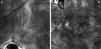

La lesión se evaluó mediante microscopía confocal de reflectancia (MCR), con la que se objetivó una desestructuración epidérmica importante, con queratinocitos de formas irregulares, en lugar del típico panal de abejas o empedrado, la presencia de células pagetoides de distribución multifocal con morfología dendrítica, una pérdida de anillos reflectantes y la ausencia de un patrón definido en la unión dermoepidérmica, así como la existencia de unas células atípicas formando nidos junturales y dérmicos, además de un infiltrado inflamatorio llamativo, con fibrosis y abundantes melanófagos (fig. 2). Con la sospecha de melanoma, se procedió a su extirpación.

La MCR es una técnica no invasiva, con una resolución muy similar a la histología convencional. Ofrece imágenes horizontales, y se puede considerar un método diagnóstico intermedio entre la dermatoscopia y la histopatología, ahorrando muchas veces extirpaciones innecesarias. Sin embargo, en estos casos, la presencia en el estudio mediante MCR de atipia celular no permite excluir el diagnóstico de melanoma. Se observan también, como es lógico, abundantes melanófagos y haces de colágeno5.